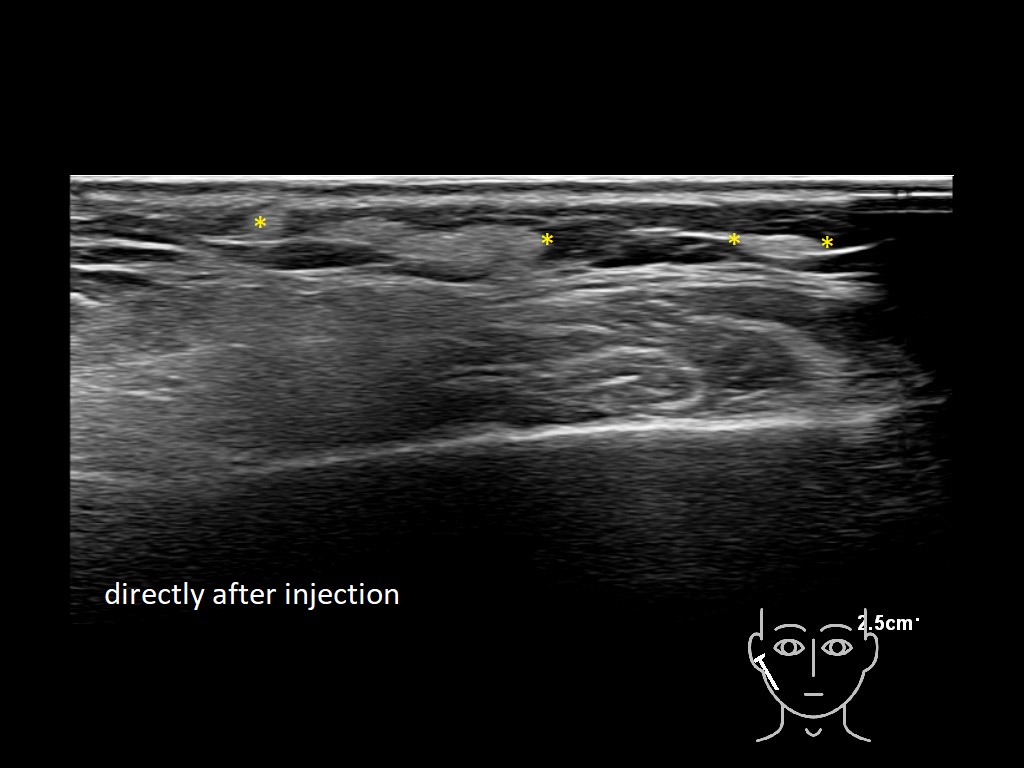

Draw in the image on the right where the fillers are located. To check if your answer is correct, please click on the secondary image.